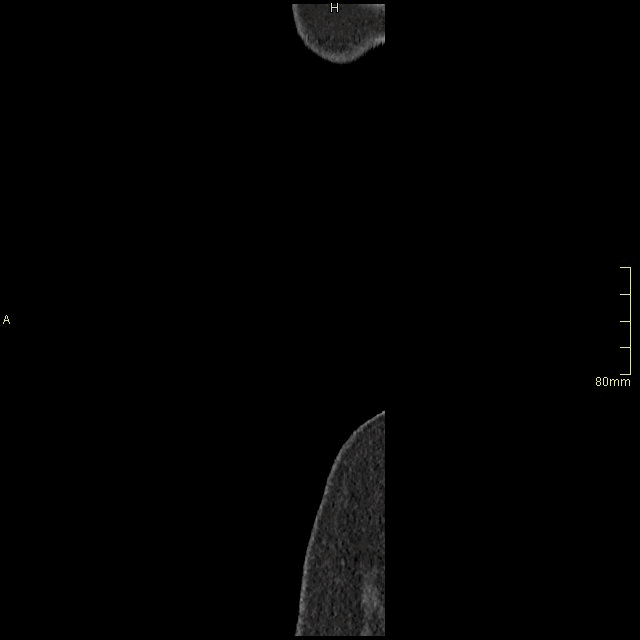

CT Abdomen/Pelvis - Non Contrast Sagittal